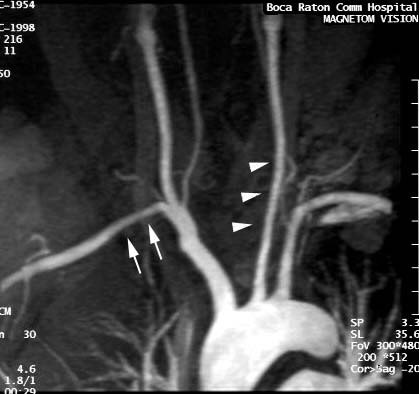

MR angiography can detect thickened walls and stenosis